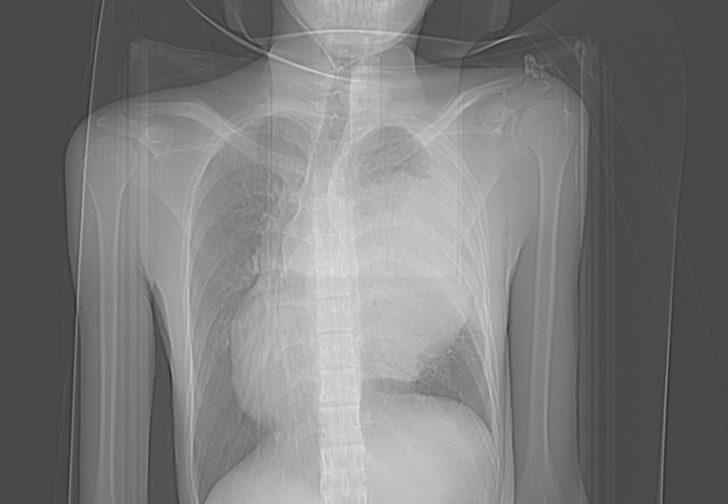

Tatil için ilçeye gelen 19 yaşındaki Endonezyalı I Made Pagehyasa Sangging, öksürdüğünde ağzından kan geldiği için Alanya Eğitim Araştırma Hastanesi'ne başvurdu. Muayene edilen Sangging'in sağ göğsünde kitle tespit edildi. Ameliyata alınan Endonezyalı hastanın göğüs kafesinden 3 kilogram ağırlığında ve 20 santimetre boyutunda bir kitle çıkarıldı.

Operasyonu gerçekleştiren Alanya Alaaddin Keykubat Üniversitesi (ALKÜ) Tıp Fakültesi Göğüs Cerrahisi Anabilim Dalı Başkanı Dr. Öğretim Üyesi Oktay Aslaner, gazetecilere yaptığı açıklamada, tetkiklerde kitlenin kalbe ve diğer organlara baskı yaptığını tespit ettiklerini söyledi.

Hastayı acil olarak ameliyata aldıklarını belirten Aslaner, sağ göğüs kafesinden iki akciğer arasında kalan 3 kilogram ağırlığındaki kitleyi aldıklarını ifade etti.

İlerleyen tıbbi cihazlar ve hastanedeki yoğun bakım olanakları ile ilerlemiş tümörlere müdahale edebildiklerini anlatan Aslaner, "Operasyonla hastanın akciğeri açıldı, kalbi rahatladı ve akciğer atar damarı normal hale geldi. Kitlenin tamamen çıkarılmasıyla hasta yeniden sağlığına kavuştu." dedi.